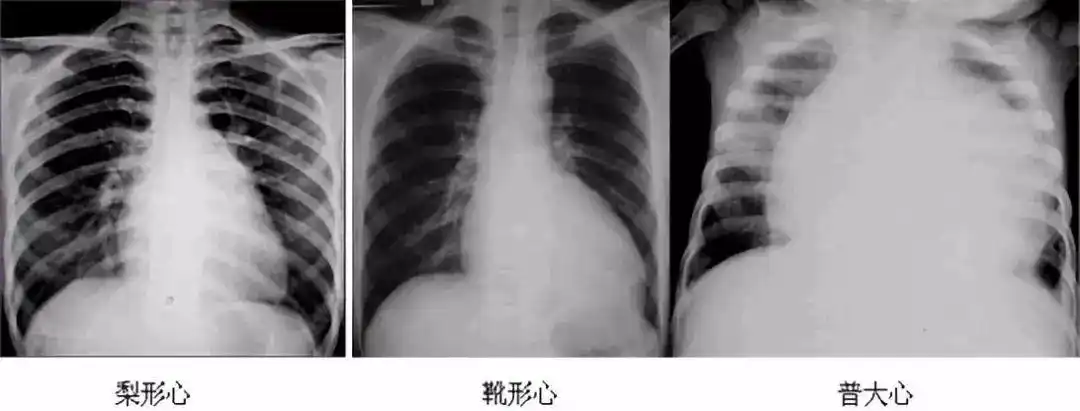

2019年医师实践技能考试x线检查